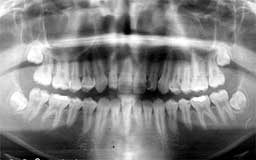

★ Uさん 38歳

当時の時代背景ということもあって、初診時38歳だったUさんのケースは少し特殊です。

メインテナンスは程度に応じて3か月・6か月・1年毎を選択するのが望ましいという保険上の

指導があったことも影響しています。多少将来が危ぶまれるものの、今すぐに何かが起こる

可能性は少ないという判断をしたUさんには3か月毎のメインテナンスを指示しました。

| Uさん 初診時 38歳 男性 歯槽骨破壊はそれほど著明ではないが、同じ年代のひとと比べれば歯槽膿漏の進行が少し 強そうな感じでした |

Uさん 20年後 57歳 長年にわたり変化のない推移だったがここ数年で急激な骨破壊を観察 |

話は戻りますが、そんななかでUさんは、唯一20年間3か月毎のメインテナンスを継続され

た貴重な存在でした。危ないから毎月に変更してもらおうと思いつつ、確実に3か月毎の予約

を守るUさんの診療態度とそれでも大きな変化もなく十分現状維持が保てている実績があって

そのままになっていました。ここ最近、左右の下顎臼歯部に急激な骨欠損が確認されたことか

ら、1か月毎のメインテナンスに切り替えることにしました。